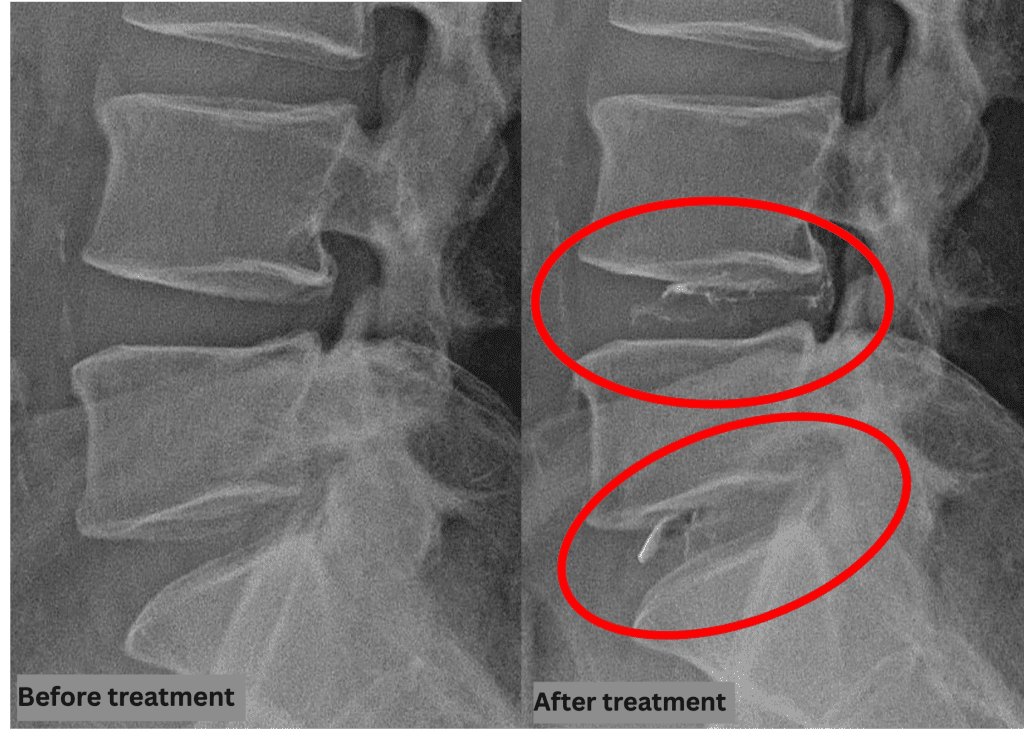

Treatment

After consulting with the patient, the Cellgel Method was performed on L4/5, 5/s.

The treatment was performed by Dr. Ohara.

The treatment took about 30 minutes.